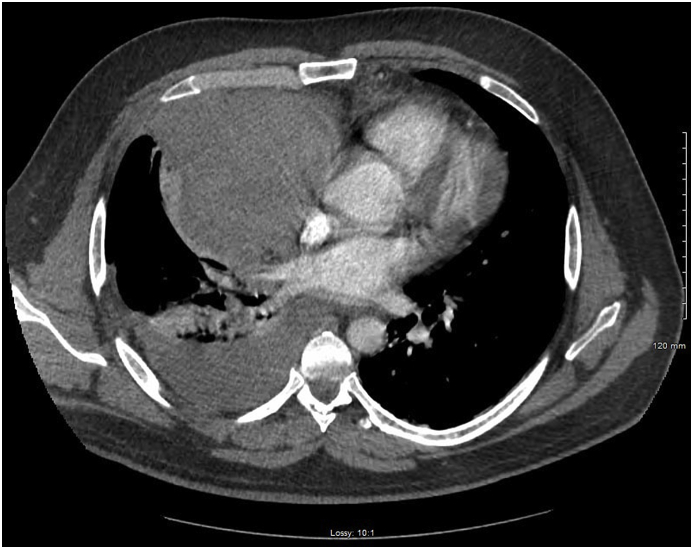

Fig. 1.

Computerized tomography of the chest showing right anterior mediastinal mass.

Fig. 2.

Computerized tomography of the chest with lung window revealing associated right hemithorax.

At the time of clinical deterioration vital signs were as following-temperature was 98.3 °F, HR 120 BPM, BP 154/93 mm Hg, respiratory rate 26 breaths per minute and SpO2 on 11 L per nasal cannula was 92%. At that time, he appeared to be in respiratory distress. There was no JVD. Chest examination revealed decreased breath sounds on the right; there was no crackles, rales or wheezing. He was tachycardic, and there was no murmurs, rubs or gallops. EKG showed new onset RBBB. There was a concern for pulmonary embolism and subsequently he underwent CT of the chest which showed a mass along the right anterior mediastinum, resulting in mass effect upon the distal right superior vena cava, and right atrium with associated right-sided hemothorax (Fig. 1, Fig. 2, Fig. 3, Fig. 4). CBC was significant for hemoglobin 13.5 g/dl. A right-sided chest tube was inserted which immediately drained one liter of blood. Over the next 24 hours, there was a minimal drainage through the chest tube. Patient subsequently had MRI of the chest which identified 8.8 cm low T1 and low T2 signal mass closely related to the right pericardium, containing multiple foci of cystic fluid without enhancement. AFP, B- HCG and TSH were within normal limits (see Fig. 5, Fig. 6, Fig. 7, Fig. 8).